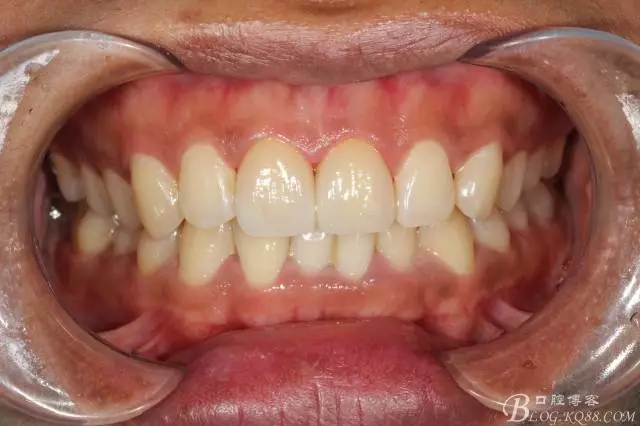

粘接完成即刻照

即刻照局部放大

兩周后復(fù)查(訴11遇冷有點(diǎn)不適,因11備牙有點(diǎn)多,露牙本質(zhì)。囑注意不要進(jìn)食過冷過熱食物。癥狀約一個(gè)月后逐漸消失。)

兩周復(fù)查局部放大